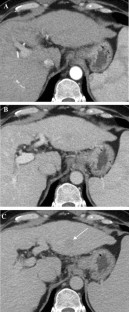

Fig. 2